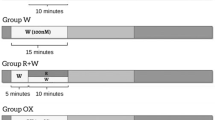

The concentration-dependent influence of GPC on cell viability and the degree of oxidative stress were tested in 3-day-old primary rat cardiac myocyte cultures exposed to acute (15 min), short-term (3 h), and long-term (24 h) GPC treatment in the 1–100 µM concentration range under normoxic conditions (n = 8–16) (Fig. 1a). One group of cells was pre-treated with GPC for 3 h and then subjected to simulated ischemia/reperfusion (SI/R). During the entire protocol, the GPC concentration range (1–100 µM) was sustained (Fig. 1b). In all experiments, GPC was dissolved in physiological saline, while the Vehicle group was treated with physiological saline solution alone in 0.1 v/v%. 2–3 isolation rounds were performed for each experimental series and data of all individual wells were analyzed.

Experimental protocol: after the isolation of the neonatal rat cardiomyocytes (NRCMs) from newborn Wistar rats, the cells were then cultured in a 10% FBS containing medium for 24 h. After the first day, the cells were kept in a 1% FBS containing medium. a Glycerophosphorylcholine (GPC) treatment was applied under normoxic conditions. Three series of cells were treated at day 3 with GPC for 15 min, 3 h, or 24 h, respectively, all prior to cell viability measurements. b GPC treatment was then applied 3 h prior to 4-h simulated ischemia (SI), and during the 2-h reperfusion period